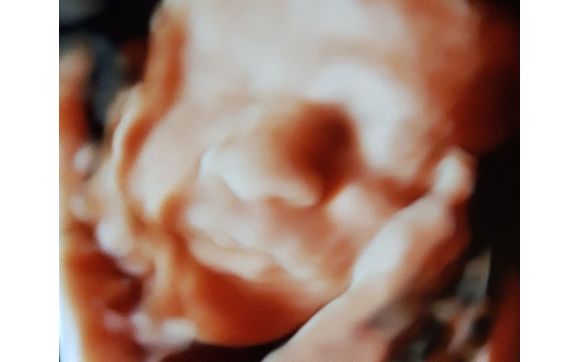

3d Ultrasound Santa Rosa Ca

Santa Rosa Prenatal 2450 W 3rd St Santa Rosa Ca 2020

Prenatal Life Imaging 3d 4d Ultrasound Services Facebook

Kicks And Giggles 3d 4d Ultrasound Center Santa Rosa Ca On Vimeo